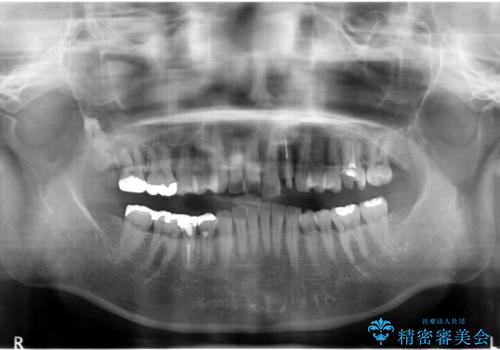

- 「 銀歯が原因で皮膚にアレルギー症状が出ている。」、と皮膚科のかかりつけ医に言われメタルフリー治療を希望され来院されました。

拡大鏡下で丁寧に銀歯の除去を行ったのち、金属を用いないセラミックインレー・クラウンによる治療を行います。